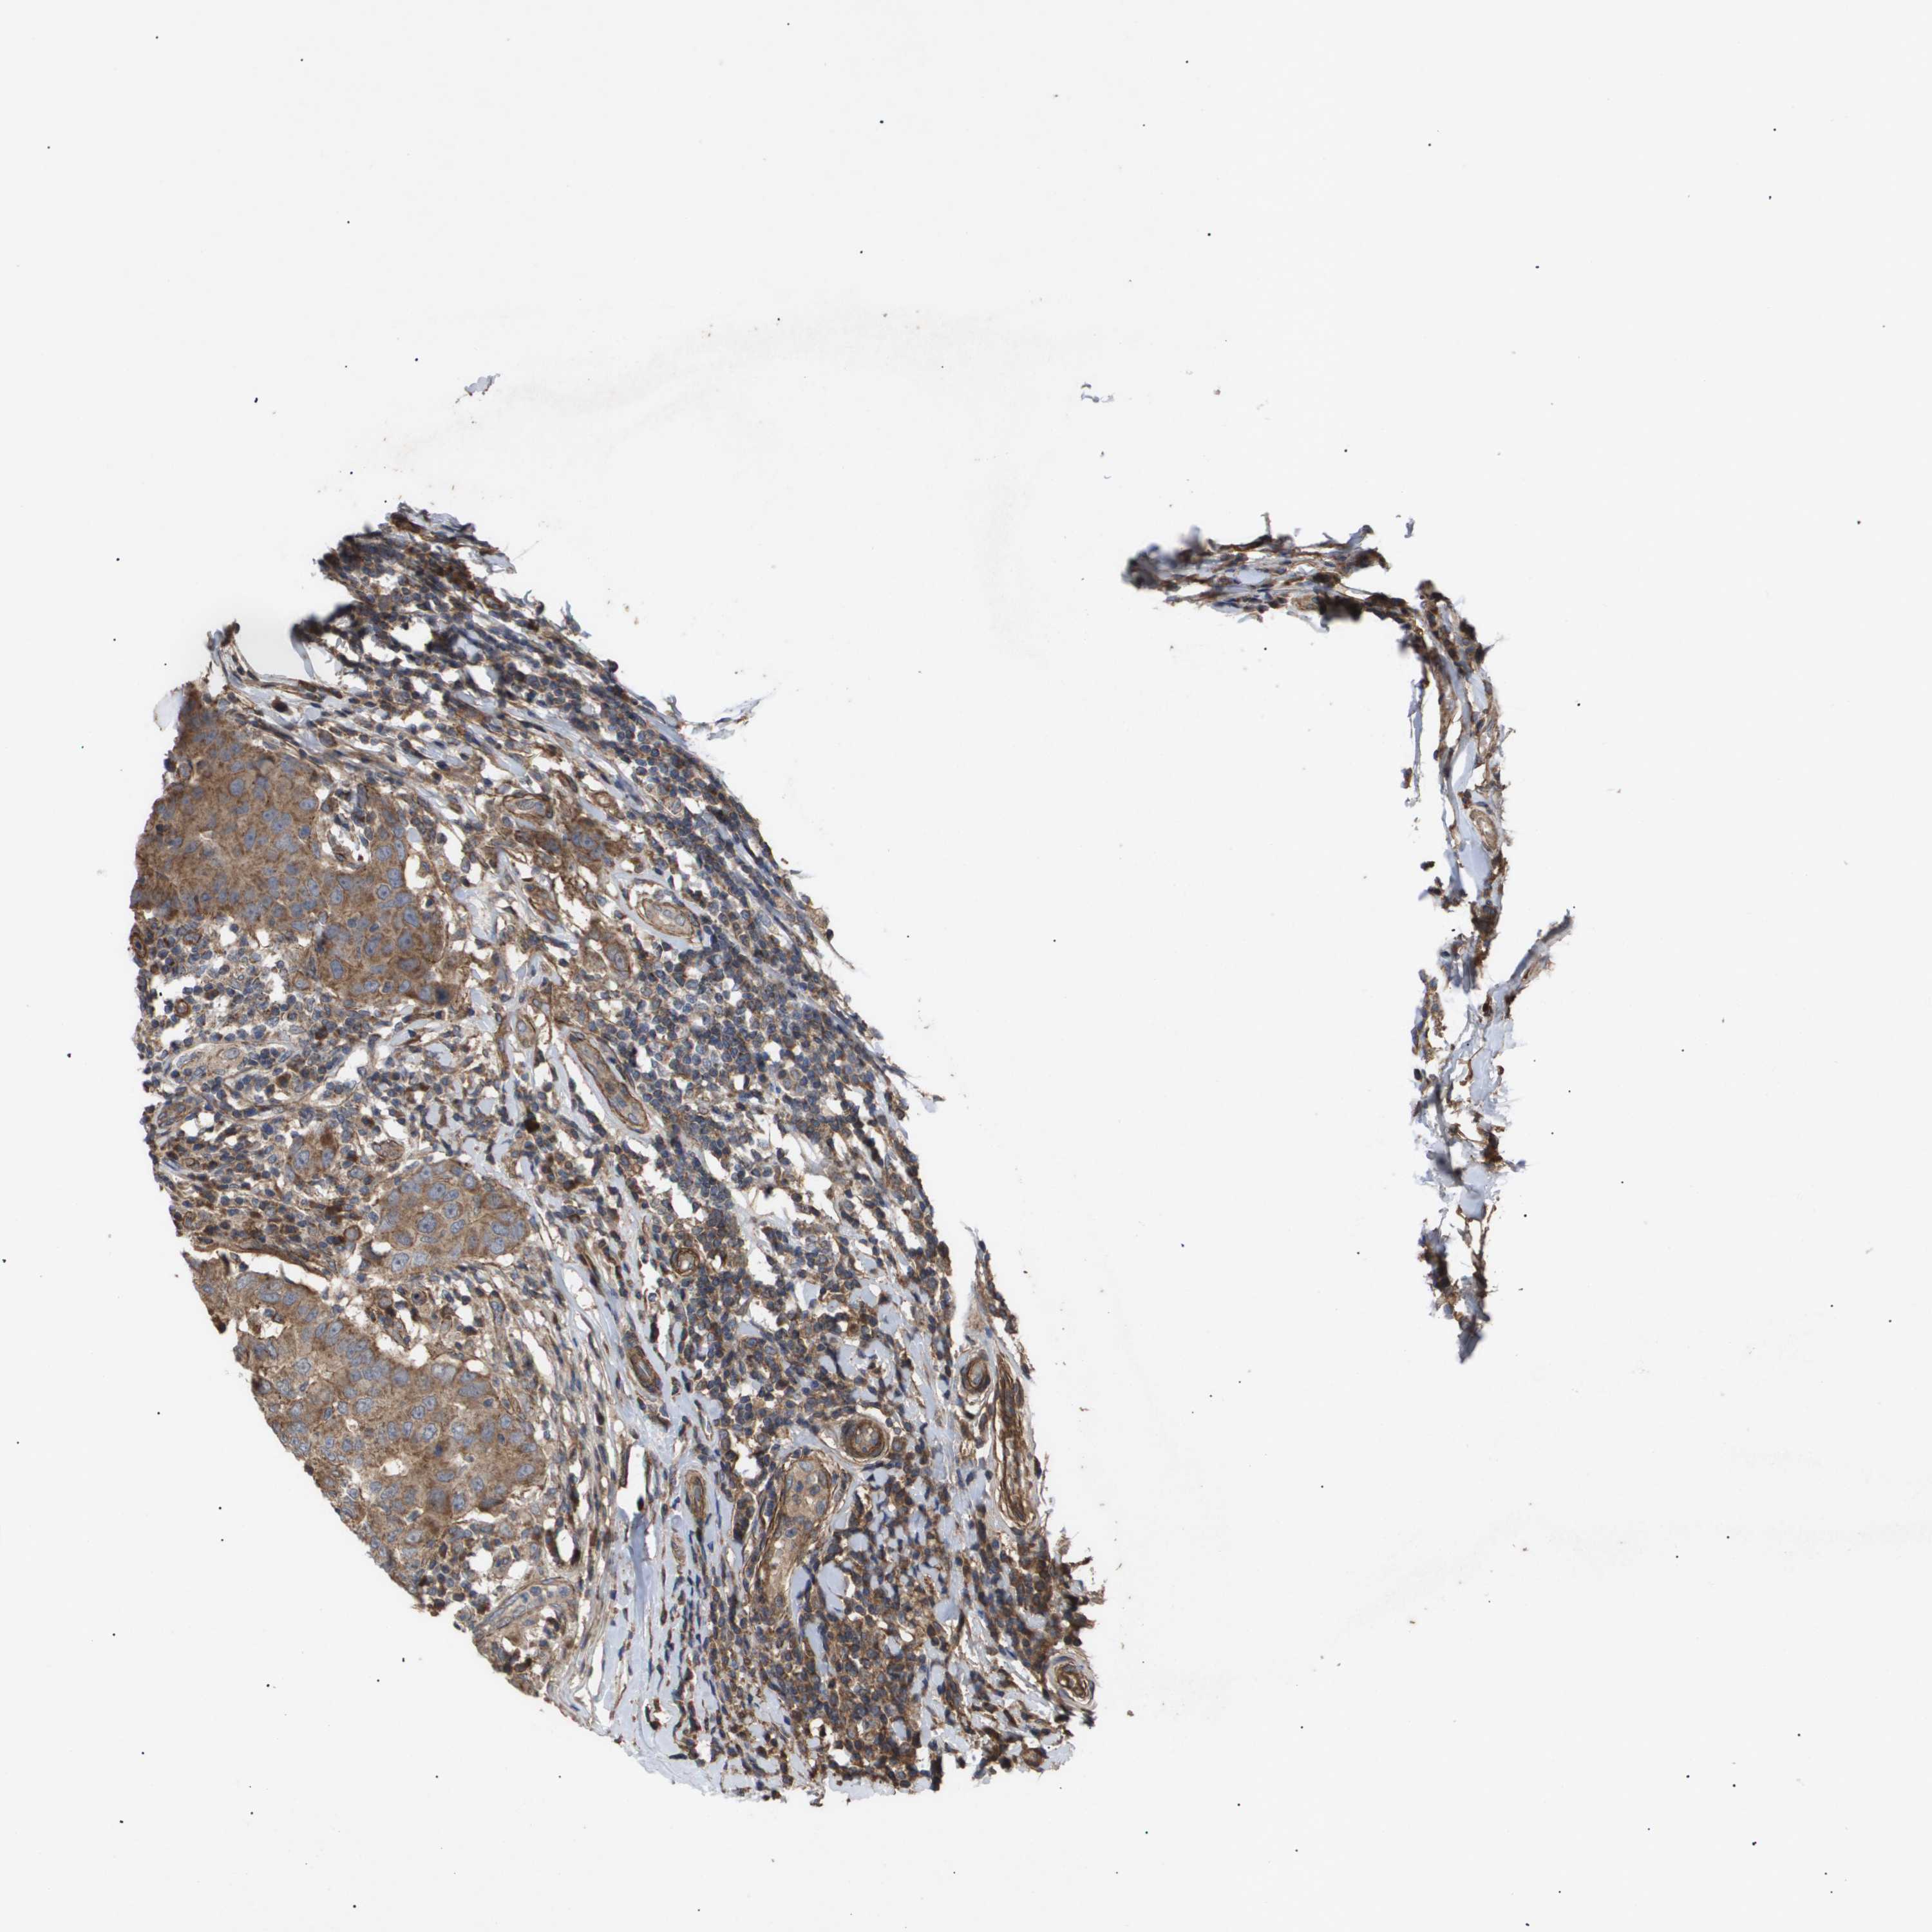

CANCER BREAST CANCER Show tissue menu

BRCA TCGA BRCA VALIDATION PROTEIN EXPRESSION